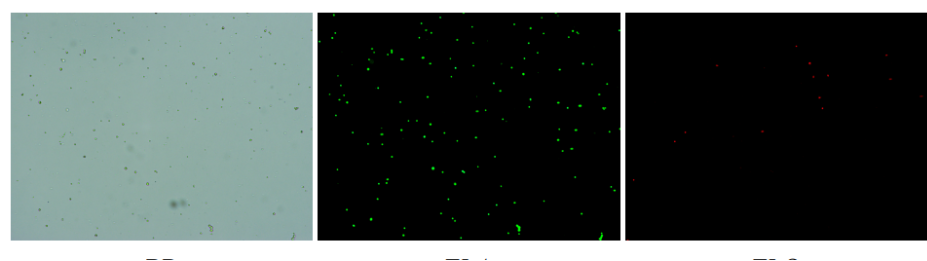

肝臟是人體代謝和解讀的器官,在體內(nèi)發(fā)揮氧化、儲(chǔ)存肝糖、合成分泌性蛋白合成等,肝臟也制造消化系統(tǒng)中之膽汁,人肝約有25億個(gè)肝細(xì)胞。但是解離肝臟組織懸液并不簡單,首先,肝臟代謝旺盛,離體后肝細(xì)胞無法進(jìn)行正常的有氧糖酵解,細(xì)胞活力會(huì)迅速下降,另外,肝細(xì)胞的線粒體很多,每個(gè)細(xì)胞大約有1000個(gè)左右,遍布于胞質(zhì)內(nèi)。因此,很難得到符合單細(xì)胞測(cè)序要求的單細(xì)胞懸液。百邁客生物在肝臟組織單細(xì)胞懸液制備方面有豐度的實(shí)操經(jīng)驗(yàn),開發(fā)了獨(dú)有的解離體系,下面來看實(shí)驗(yàn)結(jié)果:

實(shí)驗(yàn)結(jié)果

人膽管癌樣本,活性90.45%,結(jié)團(tuán)率7.2%